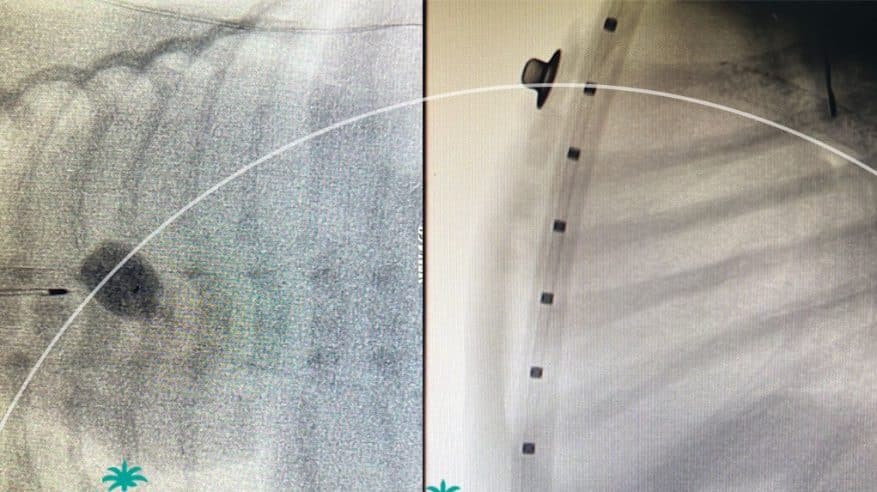

أنقذ تدخل طبي غير جراحي عاجل أجراه أطباء قسم أمراض القلب لدى الأطفال في مركز الأمير سلطان لطب وجراحة القلب بالقصيم، وعمل قسطرة قلبية لإنقاذ حياة رضيع حديث الولادة يبلغ من العمر ثلاثة أيام.

وأوضح تجمع القصيم الصحي أن الفحوصات والأشعة التي أجريت على الرضيع الذي تم تحويله للمركز من خارج منطقة القصيم ويزن ثلاثة كجم، أظهرت بوضوح أنه كان يعاني من انسداد كامل في صمام الشريان الرئوي، ما تسبب له بانقطاع تام للدورة الدموية لكامل الجسم.

وأشار التجمع إلى أنه تم خلال التدخل الطبي غير الجراحي تركي دعامة للقناة الشريانية ما بين الشريان الأورطي والرئوي بهدف إيصال الدم للرئتين، إضافة إلى توسيع ثقب أذيني لاستفادة الجسم بخلط الدم المؤكسج وغير الموكسج، وقد تكللت عملية القسطرة بنجاح، وبعد الاطمئنان على وضعه الصحي غادر المركز برفقة ذويه، وهو في حالة مستقرة ولله الحمد.